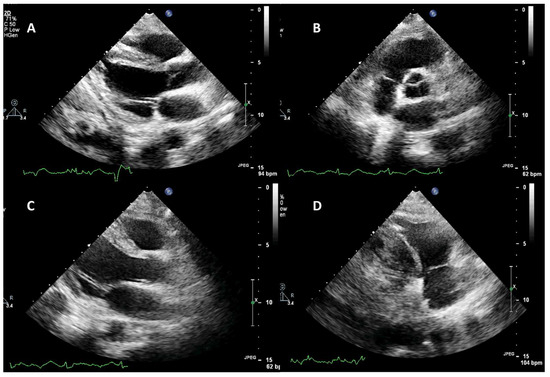

Repeat heart ultrasonography demonstrated complete resolution of the lesions attached on the aortic, mitral, and tricuspid valves (Figure 3). Transesophageal echocardiography (TEE) was performed on the 50th day (on thrombocytopenia resolution) revealing the resolution of the valvular vegetations and aortic insufficiency of a mild degree (Figure 3). The patient was weaned from the ventilator on the 60th day with a Glasgow coma scale of 15 and was discharged to a long-term health care center and ultimately weaned from the artificial airway.

Figure 3. Echocardiographic evaluation of cardiac valves on the 20th ICU day, after the patient suffered the embolic episodes. (A,B) Parasternal long-axis and short-axis view of the aortic valve. There is no residual pathology indicating the initial vegetation. (A,C) Parasternal long-axis view of the mitral valve. No pathology is identified. (D) Modified parasternal long-axis view focusing on the right chambers. There is no lesion attached to the tricuspid valve.